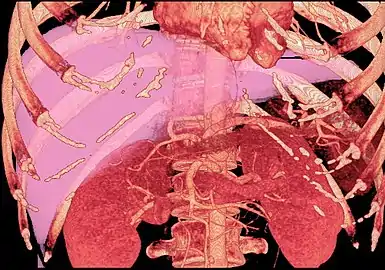

Technique

Before transplantation, liver-support therapy might be indicated (bridging-to-transplantation). Artificial liver support like liver dialysis or bioartificial liver support concepts are currently under preclinical and clinical evaluation. Virtually all liver transplants are done in an orthotopic fashion; that is, the native liver is removed and the new liver is placed in the same anatomic location.[6] The transplant operation can be conceptualized as consisting of the hepatectomy (liver removal) phase, the anhepatic (no liver) phase, and the postimplantation phase. The operation is done through a large incision in the upper abdomen. The hepatectomy involves division of all ligamentous attachments to the liver, as well as the common bile duct, hepatic artery, hepatic vein and portal vein. Usually, the retrohepatic portion of the inferior vena cava is removed along with the liver, although an alternative technique preserves the recipient's vena cava ("piggyback" technique).

The donor's blood in the liver will be replaced by an ice-cold organ storage solution, such as UW (Viaspan) or HTK, until the allograft liver is implanted. Implantation involves anastomoses (connections) of the inferior vena cava, portal vein, and hepatic artery. After blood flow is restored to the new liver, the biliary (bile duct) anastomosis is constructed, either to the recipient's own bile duct or to the small intestine. The surgery usually takes between five and six hours, but may be longer or shorter due to the difficulty of the operation and the experience of the surgeon.

The large majority of liver transplants use the entire liver from a non-living donor for the transplant, particularly for adult recipients. A major advance in pediatric liver transplantation was the development of reduced size liver transplantation, in which a portion of an adult liver is used for an infant or small child. Further developments in this area included split liver transplantation, in which one liver is used for transplants for two recipients, and living donor liver transplantation, in which a portion of a healthy person's liver is removed and used as the allograft. Living donor liver transplantation for pediatric recipients involves removal of approximately 20% of the liver (Couinaud segments 2 and 3).